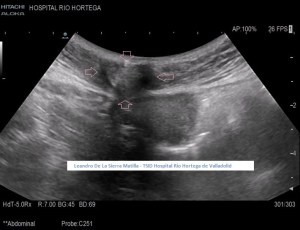

Se realiza estudio de Ecografía Abdominal protocolizado, en el que se observan entre otros hallazgos, varias lesiones esplénicas y ováricas (flechas rosas) junto con una mínima cantidad de líquido libre abdominal.(FIG 1,2 y 3)

1

2

3

Durante el estudio del peritoneo, retroperitoneo y cadenas linfáticas abdominales, observamos una lesión superficial, redondeada, heterogénea, hipo-Isoecogénica con zonas hiperecogenicas, de aspecto sólido.(FIGURA 4)

4

Cambiamos a una sonda lineal para un estudio más detallado, observando una LOE hipoecogénica con zonas híper-isoecogénicas, heterogénea, sólida, sin contenido de asas intestinales ni de grasa, con bordes mal definidos y con flujo doppler en su interior, ubicada dentro de la cavidad umbilical (FIGURAS 5, 6 Y 7)